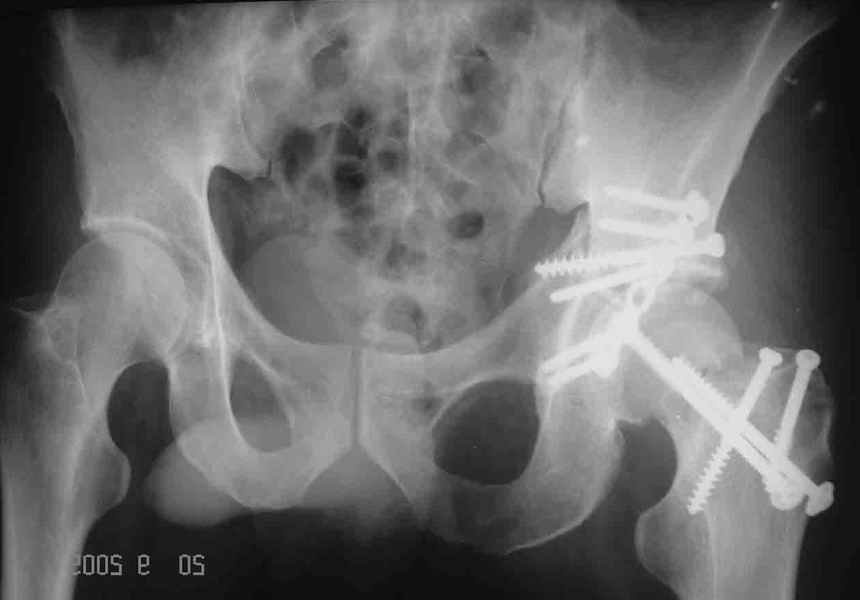

Уважаемые коллеги. Больной был оперирован в одну сессию 25 августа. Сначала на голень наложен спице-стержнвой аппарат. Затем выполнен остеосинтез вертлужной впадины Y-образным доступом. Пришлось дополнительно отсекать вертел. Шейка синтезирована спонгиозными винтами и спицами, вертел - спицами и стягивающей петлей. После операции находился на вытяжении 3 нед. Раны зажили первичным натяжением. Сейчас уже дома. Будет и дальше без нагрузки на левую ногу. Будем наблюдать в динамике. Ждем комментарии.

> дополнительно отсекать вертел. Шейка синтезирована спонгиозными

> винтами и спицами,

Мы бы ограничились фиксацией шейки 3 спонгиозными винтами. Это стабильнее пучка спиц...

> вертел - спицами и стягивающей петлей. После

Обычно мы поступаем так же, однако в этом случае имелся дефект верхней части шейкии, перелом и остеотомия вертельной области, так же с дефектами, спицы - вынужденная мера. Здесь ведь пучок спиц не вместо трех винтов, а в дополнние к двум. Эти-то два пришлось провести чуть ли не с уровня диафиза, проксимальнее было сплошное крошево.

Перелом шейки был многооскольчатйй очень медиальный, по сути шейку и вертел расколотило об подвздошную кость с кучей мелких фрагментов, вертел был полностьб вовлечен в перелом, головка заподлицо скрывалась в расширенной вертлужной впадине. Качество кости приличное. Остатки дуги Адамса с предварительно проведенными винтами я вколотил в головку и компрессировал винтами - оказалось прочно, но образовался дефект верхнего отдела шейки, который был заплнен фрагментами фиксироваными трансфрактурными спицами - отсюда пучек.

Вертел во время доступа пришлось еще рубить, т.к.

переломы распространялись чересчур дистально.

Отсюда еще пучек спиц.